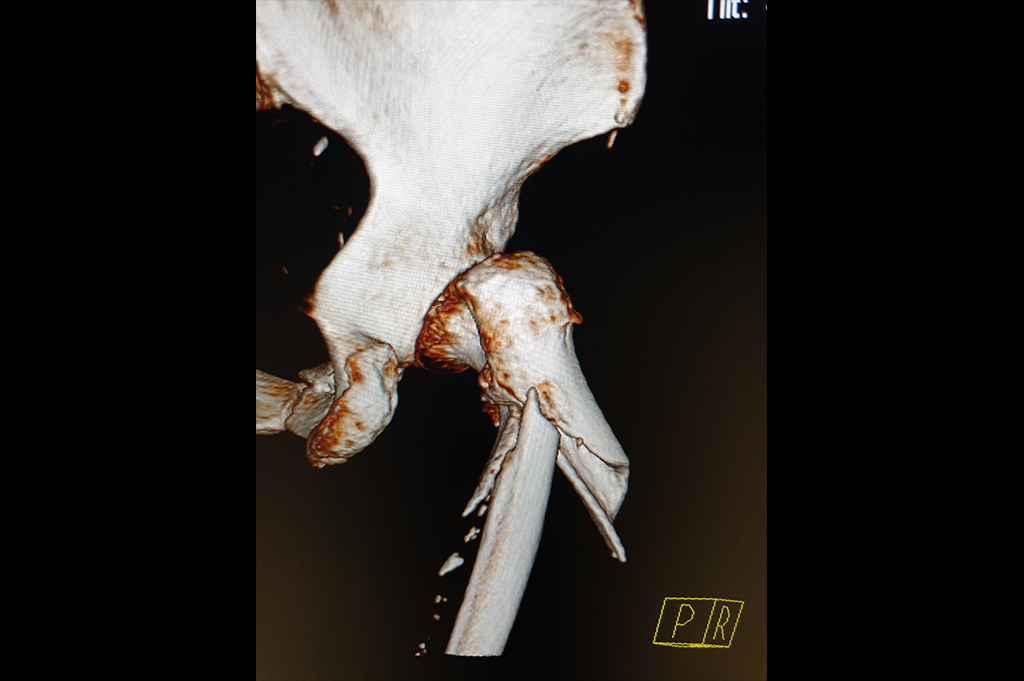

Neck Femur Fracture